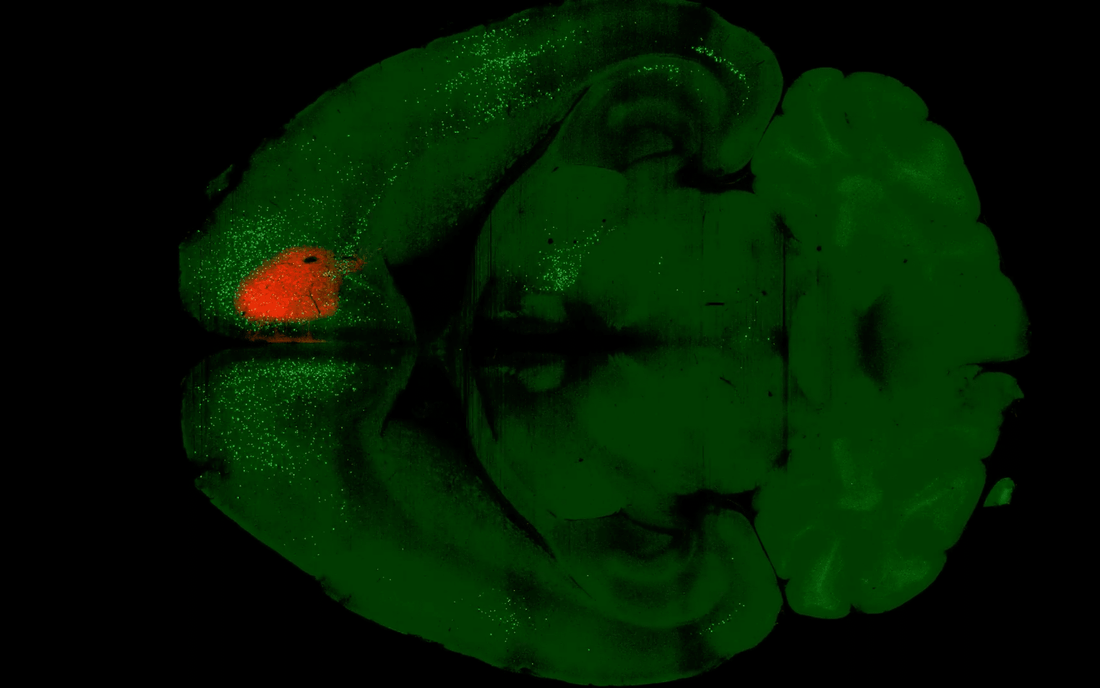

What makes this study remarkable is that instead of just watching brain activity light up on an fMRI scanner (which is cool, but limited), the Kwan lab used a viral tracing technique to literally map which neurons connect to which after a single dose of psilocybin.

They gave mice 1 mg/kg of psilocybin (roughly equivalent to a moderate human dose) and then deployed some clever molecular biology. Using modified rabies viruses that hop backward across exactly one synapse, they could see the entire network of inputs feeding into specific neurons in the frontal cortex.

Well, what they found was that psilocybin is remarkably selective about which circuits it rewires.